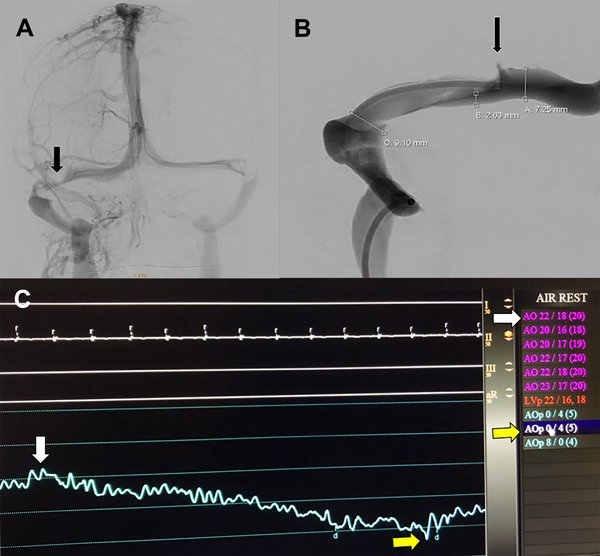

A la paciente se le había ofrecido cirugía de colocación de una válvula de derivación pero la misma rechazó esa opción. Se le realizó una angioRM con tiempos venosos que evidenció la presencia de estenosis de seno transverso derecho (figura 1) por lo que fue derivada a nuestro centro. Le realizamos una angiografía cerebral por punción radial derecha objetivando una estenosis del seno transverso derecho (figura 2A). A la vez, le realizamos un cateterismo venoso por punción femoral derecha y monitoreamos la presión a ambos lados de la estenosis del seno transverso (figura 2B). La presurometría evidenció un gradiente de presión entre el seno longitudinal superior y el seno sigmoideo derecho de 15mm de Hg (figura 2C) por lo que decidimos realizar la angioplastía del seno transverso a nivel de la estenosis.

Figura 2: A) Angiografía cerebral digital con adquisición frente en tiempo venoso. La flecha negra señala la estenosis del seno transverso derecho. B) Detalle de la venografía digital en la unión de los senos transveros y sigmoideo. Se detalla la medición del seno transverso en los segmentos estenosado y no estenosados. La flecha negra señala el catéter de acceso distal localizado en la porción proximal a la estenosis. C) Imagen del monitor durante la medición de tensión venosa en todo el trayecto del seno transverso. La flecha blanca marca la medición a nivel proximal a la estenosis (presión media 20mm de Hg). La flecha amarilla marca la medición a nivel distal a la estenosis (presión media 5mm de Hg). El gradiente de presión a través de la estenosis es de 15mm de Hg.